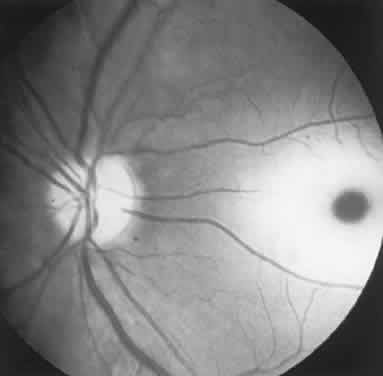

Fig. 1. A 14-year-old boy referred for occult neurologic disease or malingering who had undergone magnetic resonance imaging and psychiatric counseling. Visual acuity was 20/100 in both eyes. Fundi (A and B) show thinned rounded macular reflexes and mild pigment changes at the foveae. Fluorescein angiography (C) disclosed marked macular pigment epithelial disturbance. Diagnosis: juvenile macular degeneration (Stargardt's type).

These “hidden” retinal disorders include the following: congenital and hereditary photoreceptor or pigment epithelial abiotrophies and dystrophies; immune-mediated retinopathy associated with distant carcinoma; and an enlarging list of acute zonal occult outer retinopathies, conveniently labeled AZOOR by Gass and associates.1,2 Previously lumped as the “big blind spot syndrome,” AZOOR now encompasses a variety of heterogeneous, presumably inflammatory, retinopathies to be discussed below. Other lesions such as serous detachment of the macula (central serous choroidopathy) or cone dystrophies may be quite subtle on funduscopic examination alone, even during biomicroscopy with the use of a corneal contact lens or Hruby lens. It is in such situations that auxiliary tests of visual function, including color function, Amsler grid, photostress, ERG, and fluorescein angiography are critical in distinguishing modest lesions involving the choroid and retina from early optic nerve compression and demyelination.